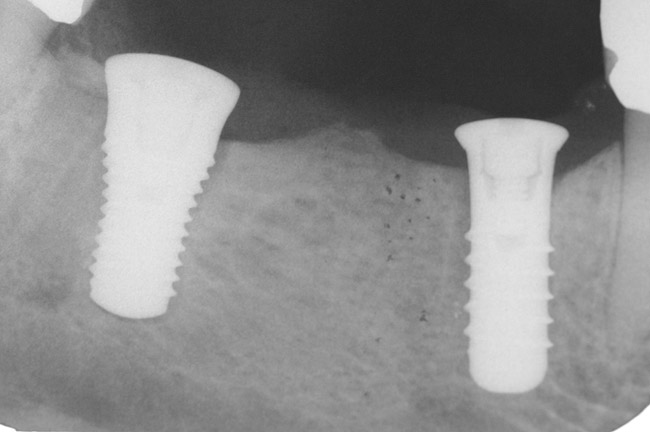

Figure 9 shows the implant placement at the time of extraction and Figure 10 shows the implant-supported fixed bridge. In one surgical procedure, the implants in the Nos. 29 and 31 positions were placed at the time of the extraction of these two teeth. The implants were restored approximately 3 months after placement.

Figure 9  Extraction of teeth Nos. 29 and 31 with immediate implants (Straumann USA, Waltham, MA) placed into the site.

Figure 9

Figure 10  Implants seen in Figure 9 restored approximately 3 months after placement.

Figure 10